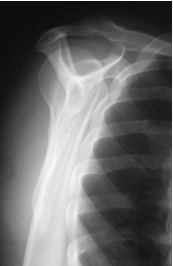

is this a normal or dislocated shoulder? in which direction is it dislocated?

dislocated, anterior